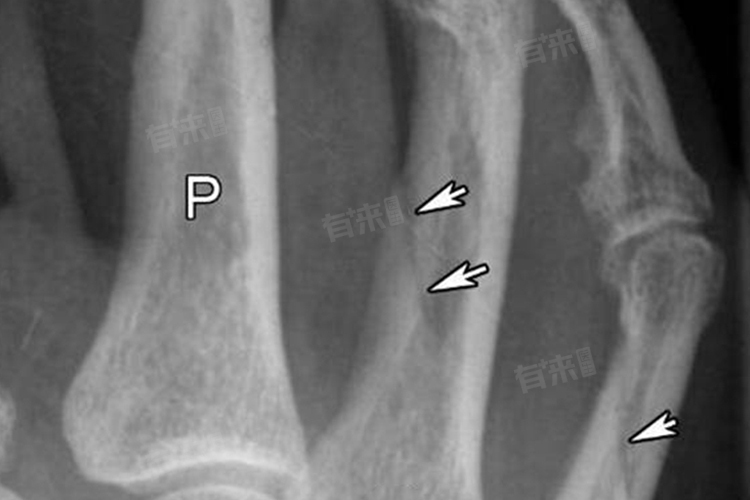

- 如果手指骨裂出现明显移位,即骨折断端发生错位,此种情况下骨裂通常不会自己愈合。需要通过手术方式进行治疗,如手法复位或切开复位内固定,确保骨折部位的正确对位和稳定促进愈合。

无论手指骨裂的严重程度如何都应及时就医,由专业医生进行诊断和治疗。在治疗过程中需要定期复查X光片,观察骨裂愈合情况。如果骨裂愈合较慢或出现移位等情况,需要及时调整治疗方案。在骨裂愈合期间需要注意营养支持,多吃富含钙质和维生素D的食物,促进骨骼的愈合。